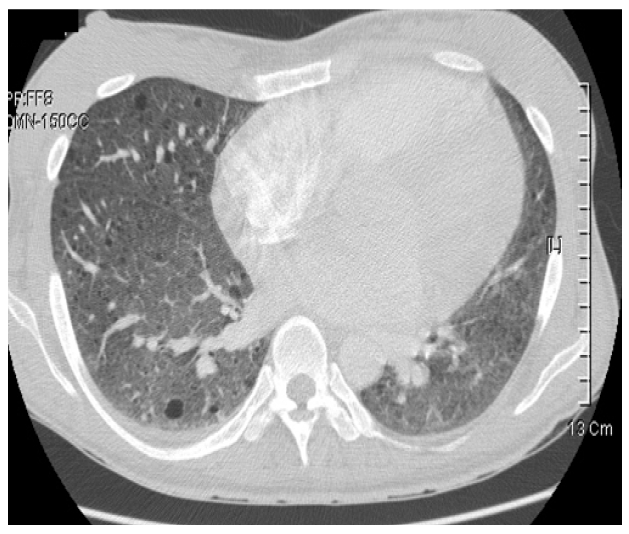

F/31

³»¿ø 2°³¿ù ÀüºÎÅÍ ½ÃÀÛµÈ È£Èí°ï¶õ, ±âħ ÁÖ¼Ò·Î ³»¿ø

ÀÌÇÐÀû ¼Ò°ß : ¾È¸é ºÎÀ§ÀÇ ´ëμº ÇÇÁö ¼±Á¾, ¾çÃø Ãøº¹ºÎ Á¾¹° ÃËÁö

ÀÌ¿Ü ÀÌÇÐÀû °Ë»ç»ó ƯÀÌ ¼Ò°ß ¾øÀ½.